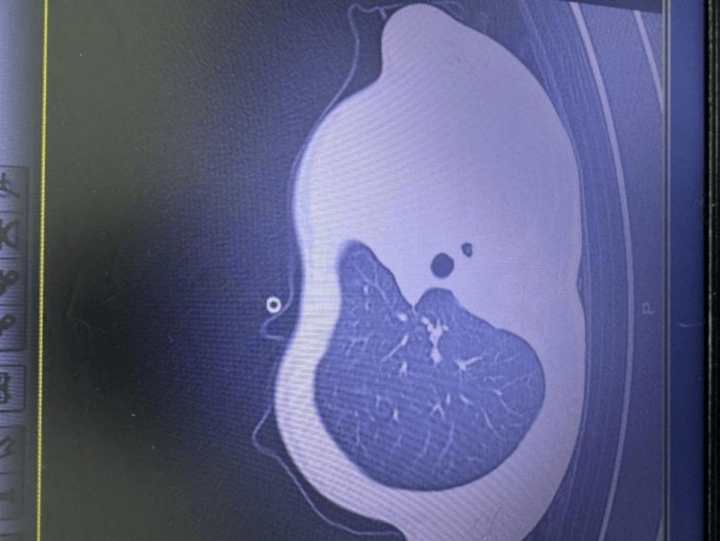

急诊检查结果让医护人员瞬间紧张:验血显示炎症指标大幅上升,胸片发现左侧肺叶几乎不工作了,影像学中变成大片白色,即通常所说的“白肺”,意味着肺功能严重受损,孩子已经缺氧,随时有窒息危险皇冠信用网正版 。

图:影像显示肺白皇冠信用网正版 了一半